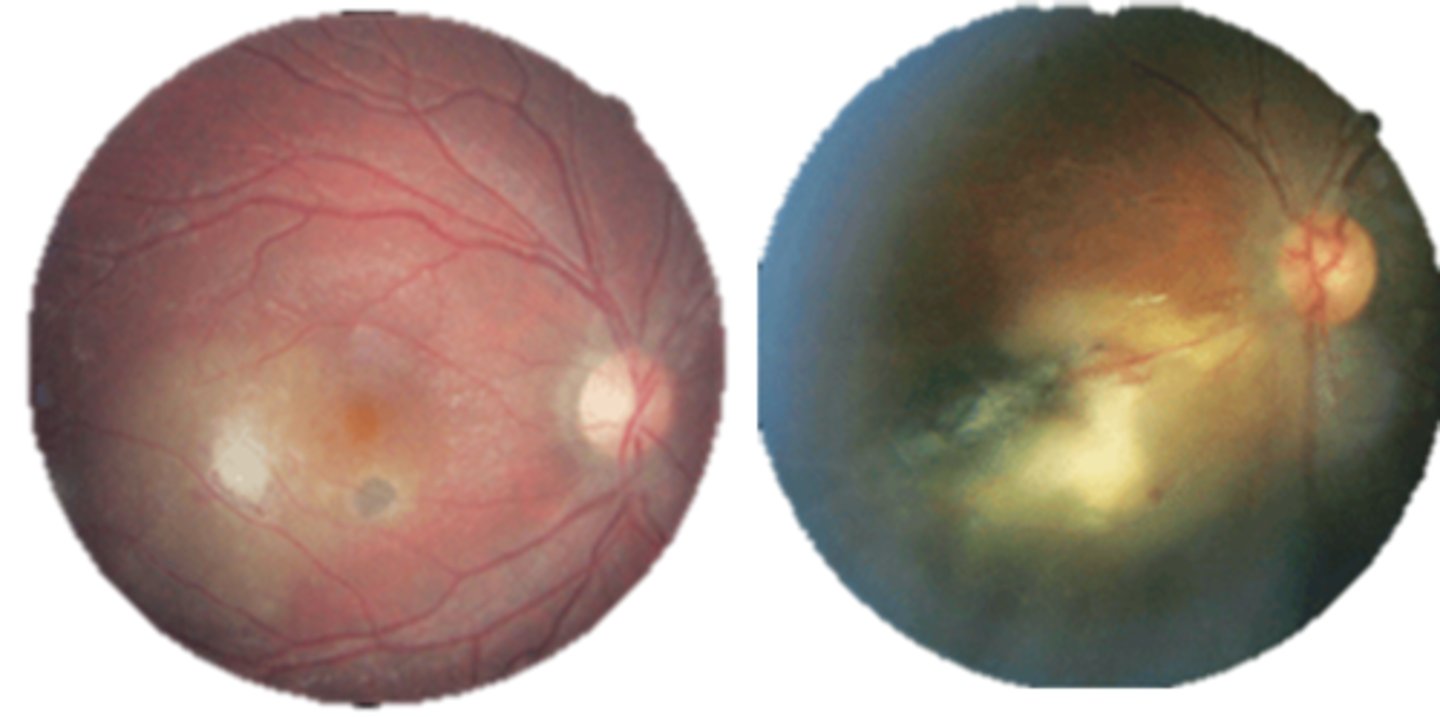

What findings of toxoplasmosis are seen here?

latent scars